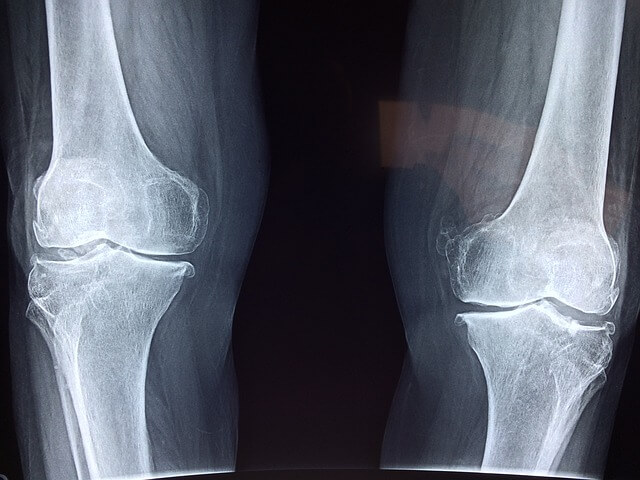

1. 퇴행성 관절염: 나이가 들면서 연골이 닳아 발생하는 질환으로, 무릎 통증, 뻣뻣함, 움직임 제한 등의 증상을 유발합니다.